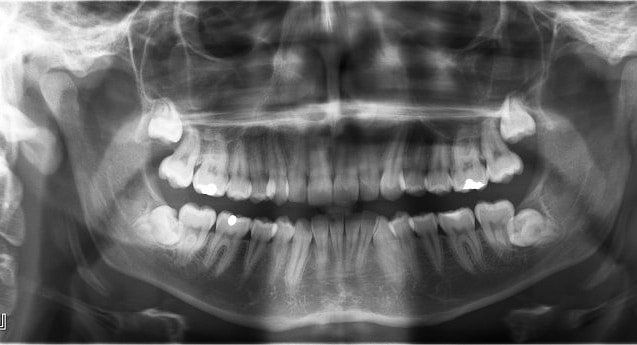

L’hyperdontie, également appelée polydontie est une anomalie relative au nombre de dents. Dans les cas de dentition normale, un adulte possède 32 dents. Les personnes atteintes d’hyperdontie peuvent en avoir bien davantage. Malheureuseme...